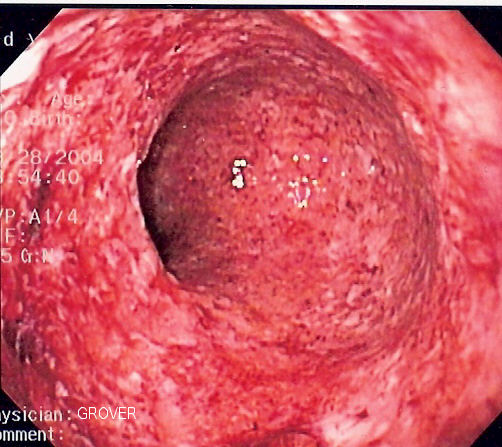

Endoscopic image of severe Crohn's colitis showing diffuse loss of mucosal architecture, friability of mucosa in sigmoid colon and exudate on wall. Photo released into public domain on permission of patient. -- Samir धर्म 07:37, 2 June 2006 (UTC) en:Category:Endoscopic images |